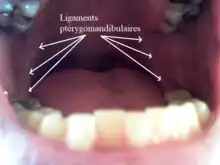

Raphé ptérygo-mandibulaire

Le ligament ptérygo-mandibulaire est une structure paire formée par le fascia bucco-pharyngé[2], un ligament de chaque côté. Sa face médiale est recouverte par la muqueuse buccale (en) de la bouche. Sa face latérale est séparée de la branche de la mandibule par une quantité de tissu adipeux. Ses bords antérieur et postérieur donnent insertion au muscles buccinateur et constructeur supérieur du pharynx respectivement[3].

Chez les fœtus, le raphé ptérygomandibulaire est toujours très proéminent. Cependant, chez les adultes, il peut devenir moins distinctif. Il est très grand et distinctif chez environ 36 % des adultes[4].